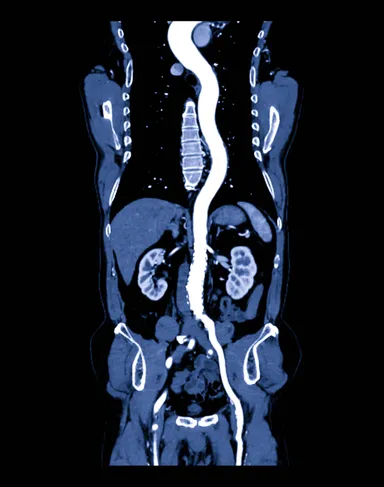

3Dimage

(3)画像だけでなく、動画での提供もできること

他社の遠隔画像システムの場合、診断結果はレポート(文字情報)とキー画像(送信画像のjpgなど)での提供と、せいぜい直交MPRが作成されるのみでした。「画像診断ラウンジ」はraw dataのまま送信可能で、キー画像も送信された画像だけでなく、動画(mp4など)、三次元画像(VR,MIPなど)、再構成画像(直交およびcurved MPR)などの提供もできるため、診断により役立てることができます。DICOM viewerはOsiriXMD(Macのみ)を使用しており、多くのポストプロセス画像をキー画像として提供可能となっています。